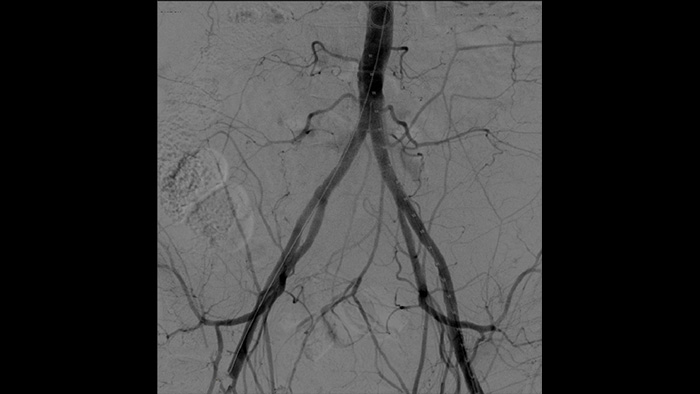

La angiografía por sustracción digital (ASD) se utiliza en procedimientos vasculares intervencionistas para ver con claridad los vasos sanguíneos mediante la eliminación de estructuras que pueden oscurecer la visibilidad de los vasos. La hoja de ruta de fluoroscopia superpone la imagen de contraste sustraída con anterioridad adquirida en la fluoroscopia en vivo, lo que le permite rastrear el dispositivo sin reinyectar el contraste.

Es más fácil ver un cable guía en comparación con nuestro antiguo sistema. Ahora se puede ver la punta y el ángulo del cable que está dando vueltas, incluso con cables de 0,014 pulgadas.

Esto se debe a que Zenition compensa lo que es metal y lo que se mueve.